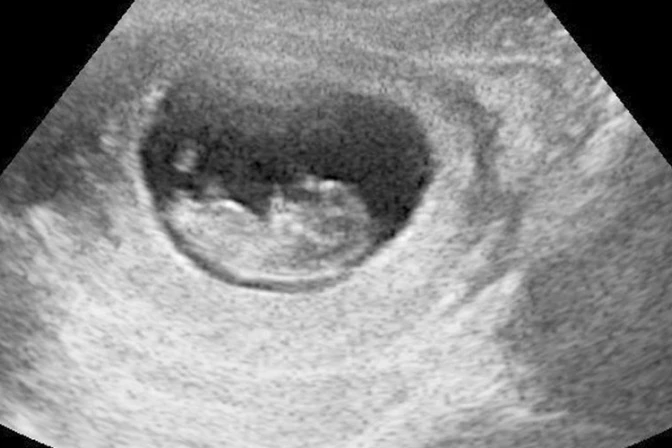

El gobernador de Georgia (Estados Unidos), Brian Kemp, promulgó la ley que penaliza el aborto desde la detección de los latidos del corazón del feto que está en el vientre materno.

La ley de "Justicia e Igualdad para infantes vivos" LIFE (Vida, por sus siglas en inglés) limita el aborto hasta las primeras seis semanas de gestación. Actualmente el aborto es legal en Georgia hasta la semana 20.